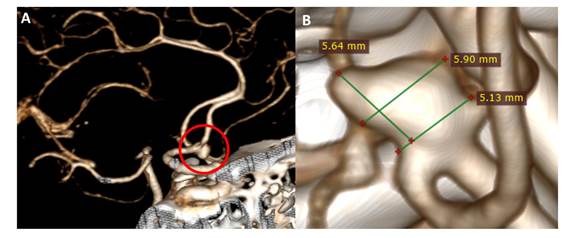

Se le realizó una TEM cerebral, en la que no se evidenció mayores hallazgos, y una angioTEM cerebral que mostró un aneurisma cerebral sacular no roto en la arteria comunicante anterior de 5,64 x 5,90 mm y cuello de 5,13 mm (Figura 1).

Figura 1 A: AngioTEM cerebral corte sagital, que muestra un aneurisma cerebral no roto de la arteria comunicante anterior. B: Medidas del aneurisma cerebral.